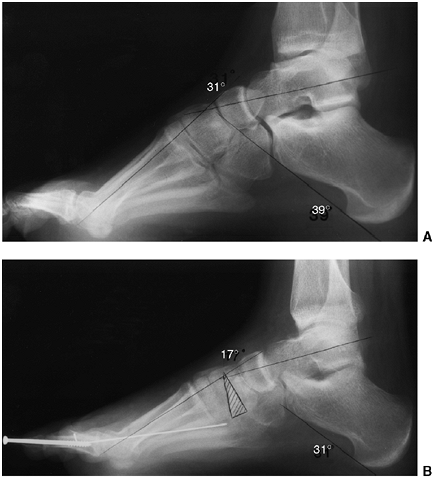

both clinically and radiographically in order to define healthy and

pathologic states. Radiographically, images are always taken in the

should be specified. In standing anteroposterior and lateral views of

the foot, the following angles should be determined (Fig. 30.3):

The lateral talocalcaneal angle (A)

(lateral view) is measured as the angle subtended by the long axis of

the talus and the plantar surface of the calcaneus. Normally, it is in

the 30 to 45-degree range. It is decreased in the varus foot and

increased in the valgus foot (Fig. 30.3B). -

The anterior talocalcaneal angle (B)

Meary angle (lateral view) is the

measurement of the angle subtended by the long axis of the talus and

the long axis of the first metatarsal on a standing lateral view.

Normally, these lines are colinear. In cases where the apex is directed

dorsally, a cavus foot is present. Cases where apex is angled

plantarward are valgus or flatfeet (Fig. 30.3B). -

Intermetatarsal angle (C)

(anteroposterior view) is the measurement of the angle subtended by the

long axis of the first and second metatarsal. This angle is generally

less than 5 degrees but is increased in deformities associated with

bunion formation (Fig. 30.3A). -

The longitudinal arch (D) (Hibb angle,

lateral view) is generally measured as an angle between the plantar

surface of the calcaneus and the first metatarsal. It is decreased in

cavus feet, particularly with a “calcaneus” deformity in which the

longitudinal axis of the calcaneus is increasingly vertical (Fig. 30.3B). -

Calcaneal pitch (E) (lateral view) is

measured as the angle between the horizontal and the plantar surface of

the calcaneus. It is an indicator of the position of the calcaneus in

stance and is particularly important in evaluating a cavus foot or

clubfoot (Fig. 30.3B).

Figure 30.3 The standard radiographs of the foot are taken in the standing position, anteroposterior and lateral views. A: On the anteroposterior view (A), the intermetatarsal angle (C) between the first and second metatarsal and the talocalcaneal angle (B) can be measured. B: On the lateral view of the foot, the lateral talocalcaneal angle, the Meary angle, the Hibb angle (D), and the calcaneal pitch (E) should be determined.